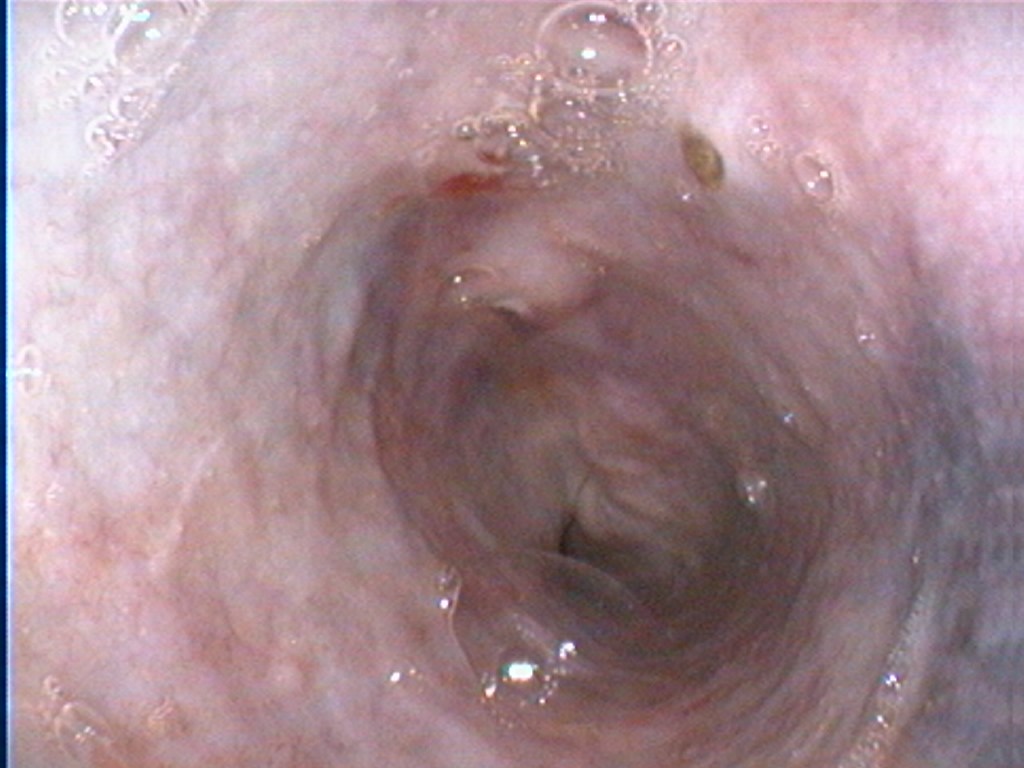

Gastroscopie à visée diagnostique sur un chien.

Présence d’ulcères gastriques, duodénum et prélèvements de muqueuse à la pince à biopsie.